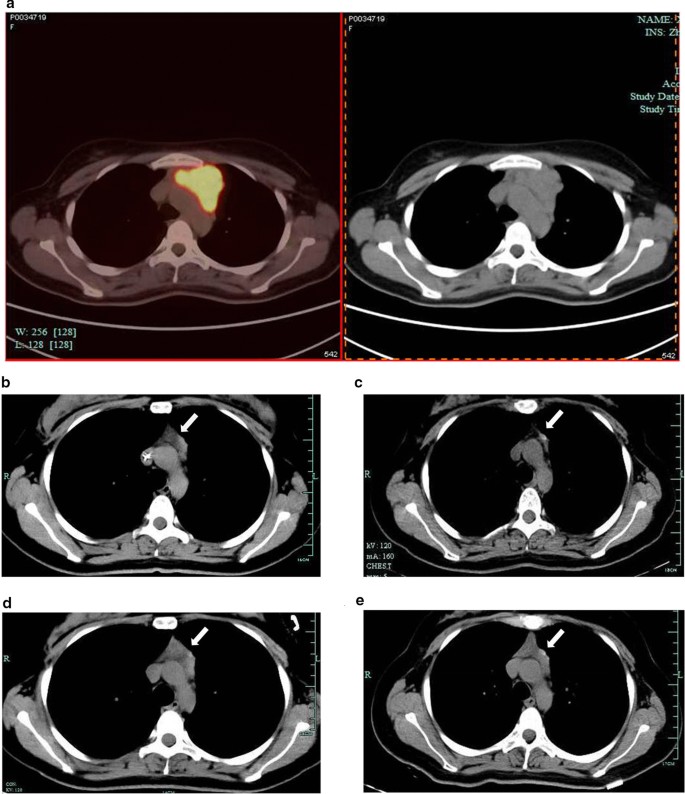

Ultrasonography showed multiple enlarged lymph nodes bilaterally around the cervical blood vessels. Cervical lymph node biopsy showed that normal structure of the lymph nodes disappeared and giant cells grew diffusely. Immunohistochemistry of the biopsy showed positive CD20, CD79a, PAX5, LCA, BOB-1, OCT-2, and MUM-1, partially positive Bcl-6 and CD30, 50% positive Bcl-2, 40% positive c-myc, 70% positive Ki-67, and negative CD3, CD5, CD10, CD21, CD15, cyclin D1 and EBER. These results suggested a DLBCL of non-germinal center B-cell origin. Fluorescence in situ hybridization (FISH) showed negative myc, Bcl-2, and Bcl-6 rearrangements. Positron emission tomography–computed tomography (PET/CT) showed multiple lymphadenopathies, beneath the right sternocleidomastoid muscle, in the right clavicle, the mediastinal thoracic entrance and the left anterior superior mediastinum, and adjacent to the aortic arch, with the maximum standardized uptake value (SUV) of 22 (Fig. 1a). In addition, focal spleen and bone marrow SUVs were abnormally increased. Considering the above test results, the patient was diagnosed with stage IVA DLBCL of non-germinal center B-cell origin according to the Ann Arbor stage system and with an age-adjusted international prognostic index of 1.

Representative PET/CT or CT images of the superior mediastinal mass in the patient’s chest during treatment. Representative PET/CT images of the anterior mediastinal lesions before treatment, showing multiple lymphadenopathies in the left anterior superior mediastinum and adjacent to the aortic arch, with the maximum SUV of 22 (a); After 8 courses of treatment, anterior mediastinal mass could be still seen (b); 3 months after ASCT, the anterior mediastinal mass disappeared (c); 6 months after ASCT anterior mediastinal mass appeared repeatedly (d); 12 months after ASCT, the anterior mediastinal mass observed similar to that 6 months after ASCT (e)

The patient received 4 courses of rituximab-cyclophosphamide, doxorubicin, vincristine, and prednisone chemotherapy (R-CHOP-21) starting on September 24, 2016. The mid-term PET scan after the 4 R-CHOP-21 courses showed that the mediastinal mass adjacent to the aortic arch still existed with the SUV value reduced from the maximum of 22 to 2.6 (hepatic blood pool SUV = 2.2). Given the condition, the patient was subsequently given another 4 courses of R-CHOP-21. At the end of the 6th course of chemotherapy, peripheral blood stem cells were collected following 7.5 μg/kg granulocyte colony stimulating factor (G-CSF) mobilization, and 5.4 × 106/kg hematopoietic stem cells in total were collected. After completion of 8 courses of the chemotherapy, CT scan showed that thickened soft tissue could be seen in the original lesion of the anterior mediastinum (Fig. 1b), while another PET/CT scan showed that the soft tissue inside the left anterior mediastinum and the anterior superior mediastinum was slightly thickened, with slightly increased local density and mild elevation of fludeoxyglucose (FDG) metabolism (SUV = 2.3, hepatic blood pool SUV = 1.9). Tumor activity was therefore could not be ruled out. After discussing the situation with the patient and her family, an autologous hematopoietic stem cell transplantation (ASCT) was performed on July 24, 2017. The treatment regimens included 300 mg/m2 carmustine (BCNU) (day − 6), 100 mg/m2 etoposide (VP16) (day − 5 to day − 2), 200 mg/m2 cytarabine (Ara-c) (day − 5 to day − 2), and 140 mg/m2 melphalan (day − 1).

Further CT scan showed that the thickened soft tissue in the anterior mediastinum almost disappeared 3 months after ASCT (Fig. 1c), while an anterior mediastinal mass was detected again 6 months after ASCT (Fig. 1d), suggesting a potential recurrence of the original lesion. On January 31, 2018, a multi-disciplinary team (MDT), composed of specialists from the Imaging Department (including the specialists from the PET center), Thoracic Surgery Department and the Hematology, was built to make a discussion regarding the condition of the patient. They thought the anterior mediastinal mass was unknown and might be thymus tissue or tumor tissue, and a further observation or a biopsy was required to define. Following another discussion regarding the condition, a video-assisted thoracoscopic surgery was performed for biopsy of the soft tissue of the anterior mediastinum for pathological examination and the result showed thymus tissue (Fig. 2). Final chest CT scan 12 months after ASCT showed an anterior mediastinal mass similar to that on the previous chest CT image (Fig. 1e). The patient has achieved disease-free survival so far. The timeline of the patient is shown in Additional file 1.